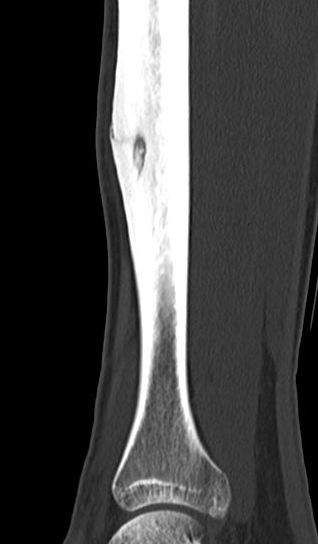

CT

Best investigation

- lucent nidus surrounded by dense bone

Osteoid osteoma tibia